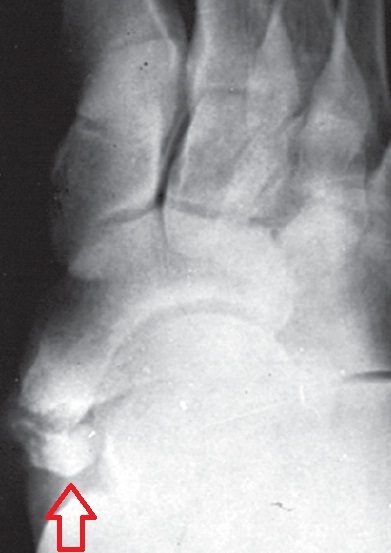

이 질환은 중간 발 안쪽에 있는 주상골(舟狀骨 - 돛단배모양의 뼈라는 뜻)에 덤으로 조그만 뼈 조각이 더 있는 병인데, 발 안쪽이 튀어나와서 진단이 어렵지 않다.

이 뼈 조각은 대개 중학교 2학년 쯤 되는 시기(약 13,14세 )에 나타나는 것이 일반적인데, 이 뼈가 있다고 해서 모두 문제가 되는 것은 아니고, 발을 한번 제대로 삔 후에부터 통증이 발생해서 이 뼈에 붙는 아치를 만들어주는 중요한 힘줄(후경골건 )을 망가뜨리면서 평발을 되고 통증, 순발력, 지구력 등 을 떨어뜨리는 경기력 저하를 일으키게 된다. 우리나라를 대표하는 올림픽 마라토너도 이 부주상골이 있었음에도 불구하고 금메달까지 딴 일은 유명한 일화다.